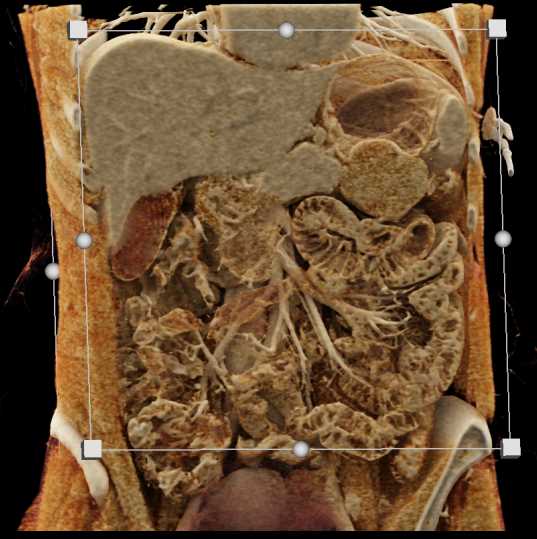

Neuroendocrine Tumor Pancreas